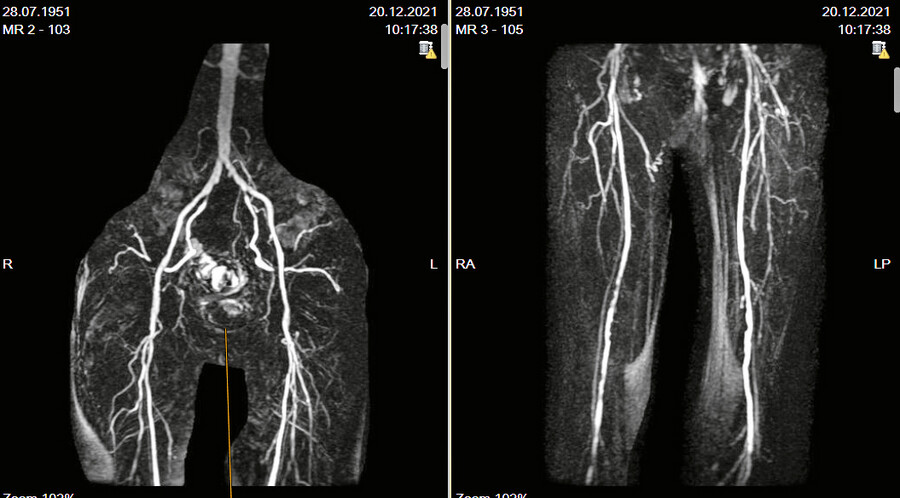

Eine bildgebende Diagnostik (wie arterielle BBA mit Option zur PTA lehnte der Patient ab) zeigte einige Wochen später folgendes Bild, auch zur Veranschaulichung der arteriellen Perfusion für den Patienten (Abb. 13).

Eine Verifizierung der dargestellten Stenosen/Gefäßabbrüche/Verschlüsse durch eine selektive arterielle Becken-Bein-Angiografie lehnte der Patient ab und wünschte unverändert die Fortführung der Therapie mit regelmäßigem chirurgischem Wunddebridement, Desinfektion, Fortführung der antibiotischen Therapie und Entlastung/ Ruhigstellung der Wundregion.